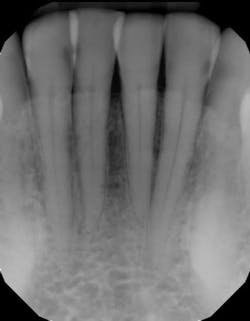

For example, one patient of a general dental practice had a caries-free history for 35 years. He ceased smoking traditional cigarettes and decided to vape as he thought this was a healthier alternative. Within a year, cervical enamel demineralization and interproximal lesions were present on the mandibular anterior sextant, consistent with the primary point of contact of the e-liquid aerosol (figure 2).

Figure 2: Effects of e-cigarette usage